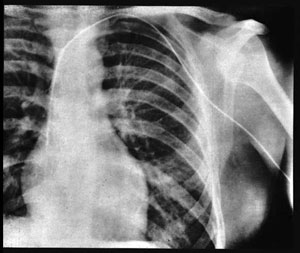

In 1929 in the basement of the Eberswaled Hospital in Germany, surgical resident Werner Forssmann inserted a ureteral catheter tube into his elbow, feeding it through a vein up to his heart. He used a mirror as his assistant, since he had restrained his nurse to the operating table. He then took an x-ray of his chest (at left) to determine the catheter had indeed made it to the right atrium.